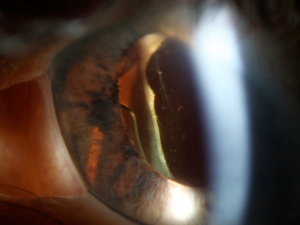

Presentation of glaucoma in aphakic/pseudophakic eyes may be very similar to those in phakic eye, and a thorough patient history complete with disease onset in relation to ocular surgeries is necessary. Some of the ways to evaluate a patient presenting with glaucoma include utilizing gonioscopy to visualize angle morphology and presence of lens fragments, ultrasound biomicroscopy (UBM) and Scheimpflug video imaging to evaluate the location and stability of the lens behind the iris[7][8]. In a published series of UBM in UGH patients, 8/9 study patients had posterior chamber intraocular lens. In 5 cases, UBM visualized at least one of lens haptics was in contact with posterior iris pigment epithelium and in remaining, one of the haptics was embedded into ciliary body[7].